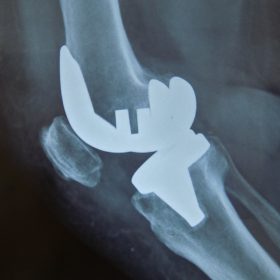

Σε αυτό το σημείο η Αρθροπλαστική Γονάτου αποτελεί μονόδρομο.